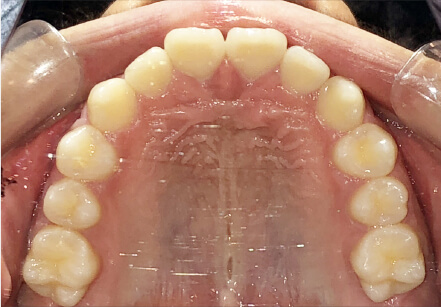

叢生の症例

/

相談内容

カウンセリング・診断結果

治療内容・方法

術後の経過・現在の様子

治療のリスク

費用・治療期間